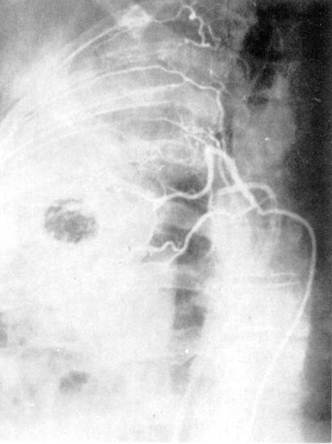

АНГИОПУЛЬМОНОГРАФИЯ

Ангиопульмонография — способ контрастного исследования сосудов малого круга кровообращения. Чаще всего показания к ангиопульмонографии определяются как дифференциально-диагностические: при пороках развития легкого, нагноительных заболеваниях, бластоматозном процессе. Она дает также возможность определить функциональное состояние паренхимы легкого, оценить гемодинамику Различают четыре способа ангиопульмонографии: 1) общую ангиопульмонографию, выполняемую путем внутривенного введения контрастного вещества или посредством ангиокардиографии из правого желудочка сердца; 2) селективную ангиопульмонографию, выполняемую из ствола или ветвей легочной артерии; 3) суперселективную ангиопульмонографию, включающую контрастирование из долевых, сегментарных ветвей легочной артерии; 4) окклюзионную ангиопульмонографию, выполняемую при заклинивании субсегментарной или лобулярной ветви легочной артерии концевой частью сердечного катетера или при блокировании баллоном катетера магистральной ветви легочной артерии. Ангиопульмонография производится в рентгенооперационных, обеспечивающих телевизионный рентгенологический и физиологический контроль, оснащенных автоматическими инъекторами для быстрого, дистанционного и синхронного с рентгенографией введения контрастного вещества (уротраст, верографин и др.) в сосуды и сердце. Сердечный катетер вводится в сосуды, как правило, чрескожно-чрезбедренным способом.

Рис. 6. Ангиопульмонография.

а — артериальная фаза; б — капиллярная фаза; в — венозная фаза.

Рис. 7. Селективная ангиография бронхиальных артерий.

Контрастное исследование сосудов средостения включает в себя флебографию и аортографию. Флебография выполняется с учетом характера патологического процесса, выявляемого при помощи рентгенографии, томографии, бронхографии. При указании на вероятное поражение лимфатических узлов переднего средостения выполняют верхнюю кавографию и контрастное исследование внутренних грудных вен, а при подозрении на поражение лимфатических узлов заднего средостения — азигографию. При анализе ангиопульмонограмм обращают внимание на пофазовое продвижение контрастного вещества по различным регионам легкого: легочной артерии, капиллярного русла, венозной системы малого круга кровообращения (рис. 6).

При селективной ангиографии бронхиальных артерий катетер вводится в грудную аорту и далее — до устья бронхиальных сосудов; введение контрастного вещества осуществляется с помощью автоматического инъектора. Сериография, проводимая, как правило, в переднезадней проекции, может быть дополнена рентгенограммами в боковой или косой проекциях в зависимости от задач исследования (рис. 7).